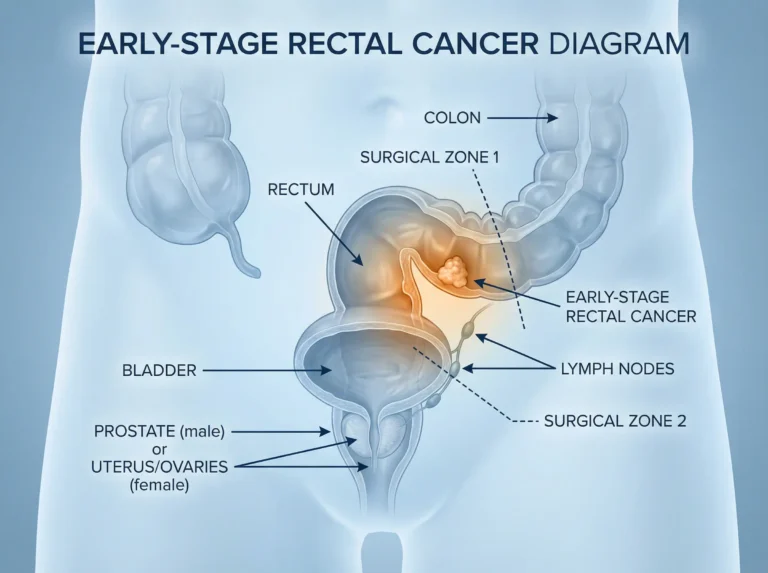

Introduction Colon cancer surgery in Mira Road, The Colon cancer is one of the most common types of cancer worldwide, and timely…

Best Colorectal Cancer Surgery In Mira Road Understanding What You’re Going Through Colorectal cancer surgery in Mira Road provides advanced treatment options.…

What This Blog Is About If you or someone you love has been dealing with symptoms like blood in the stool, pain…

Understanding What You’re Going Through If you or someone close to you has been diagnosed with colorectal cancer, it’s completely normal to feel…